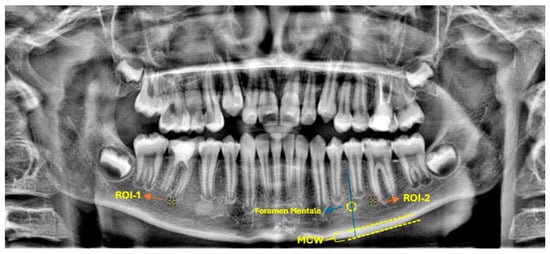

Before proceeding with fractal analysis, bilateral morphometric evaluations were meticulously performed at the level of the mental foramen. These evaluations encompassed measurements of MCW, mental length (ML), and the panoramic mandibular index (PMI).

MCW was precisely defined as the perpendicular thickness of the mandibular cortical bone, measured from a tangent line drawn along the inferior border of the mandible to a point intersecting the midpoint of the mental foramen. ML was represented as the vertical distance between the lower margin of the mental foramen and the inferior border of the mandible. The PMI was subsequently calculated as the ratio of MCW to ML. All measurements were performed by a single calibrated examiner, adhering to standardized image settings to guarantee consistency and minimize potential measurement error.

2.8. Fractal Analysis

Fractal analysis was executed using ImageJ software (version 1.54; National Institutes of Health, Bethesda, MD, USA), which is freely accessible via the NIH website. The methodology for estimating the FD was based on the box-counting technique, as originally described by White and Rudolph. For each panoramic radiograph, a square ROI of 30 × 30 pixels was consistently selected approximately 1 mm apical to the root apex of the treated tooth (Figure 2).

Figure 1. Representative panoramic radiograph demonstrating the selection of ROIs (region of interest) and the methodology for radiomorphometric measurements.

Figure 2. Representative panoramic radiograph demonstrating the selection of ROIs and the methodology for radiomorphometric measurements.